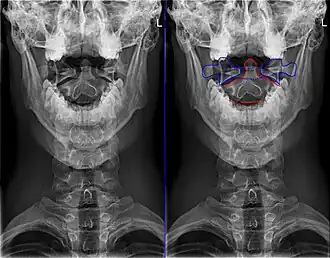

Het is de draaier van de wervelkolom. De axis maakt met zijn tand (dens axis) gewricht met de eerste (C1) halswervel of atlas. Dit is in zijn geheel de articulatio atlantoaxialis. Op de voor- en achterzijde van de dens axis bevindt zich een gewrichtsvlak: de facies articularis anterior die articuleert met de fovea dentis van de atlas, en de facies articularis posterior waartegen het ligamentum transversum atlantis komt te liggen dat de dens op zijn plaats houdt. Atlas en hoofd draaien om de dens axis, een beweging die overeenkomt met het nee-schudden. Verder heeft de atlas dezelfde kenmerken als de andere halswervels.